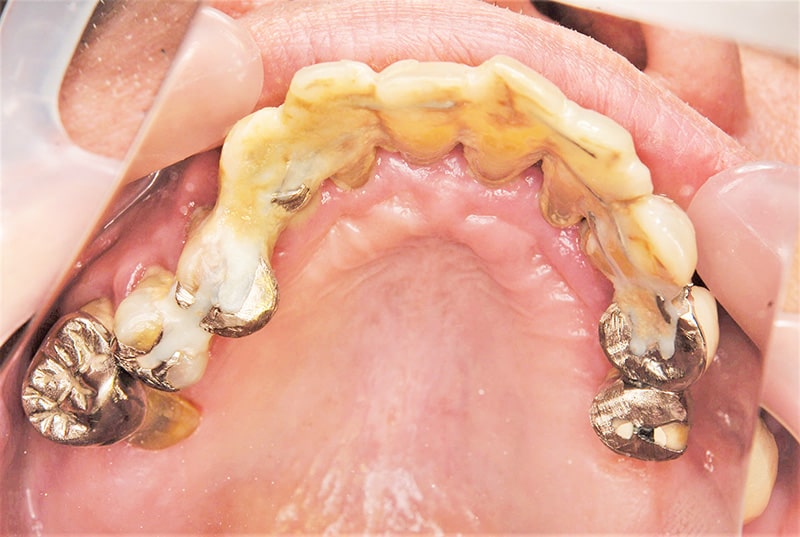

症例2【70代女性】主訴 義歯がわずらわしい・しっかり噛みたい

治療前

治療後(2年経過)

※説明

主訴 上顎のみ部分義歯を使用しているが、入れ歯が煩わしい、固定制のインプラントにして欲しいと来院。

左右上顎第一大臼歯相当は、骨の高さが不足しており、ソケットリフト(骨造成)の必要があり、左右第一小臼歯、第一大臼歯支台のインプラントブリッジを提案。

採血で得られた、CGFメンブレンとAFGブロック(人工骨β‐TCPとAFGを混ぜたブロック)を使用し骨を挙上し、インプラントを埋入。

右下のブリッジも、短根歯で動揺が激しい為に抜歯し、インプラント埋入。

上顎の免荷期間は約4ヶ月、下顎の免荷期間は約2ヶ月を経て、仮歯を装着、リハビリをし、メタルボンド(金属焼付ポーセレン)を装着。

費用 280万(オペ・ソケットリフト・人工骨・採血による濃縮血小板生成・仮歯・最終補綴物まで含む)